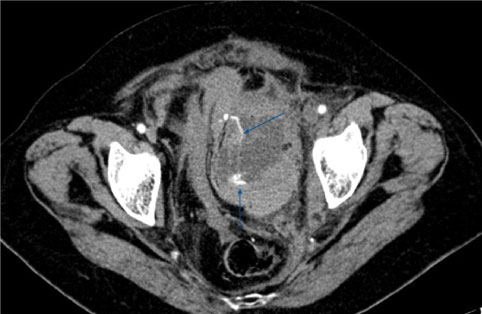

A 25-year-old male was transferred to the Emergency Department of the tertiary Regional Hospital of Nikea after a high-energy motor-vehicle collision. Initial management was based on the protocols of Advanced Trauma Life Support (ATLS). At first evaluation, he was haemodynamically unstable with sinus tachycardia and 80 mmΗg systolic blood pressure requiring bolus infusion. The patient responded rapidly to the infusion of 1 lt of Ringer's solution and his hemodynamic condition stabilized having a heart rate of 90 and 80 mmHg mean arterial pressure. At physical exam, he had a mild left upper quadrant abdominal pain without signs of peritonitis and mild pelvic tenderness without instability. His airway, lungs and brain presented no clinical radiological damage, GCS 14/15. Further evaluation for injuries showed a complete displaced right femoral shaft fracture causing deformity. Inline longitudinal traction was applied, realigning the extremity and maintaining limb perfusion. He reported no significant past medical history and denied any medication. A FAST scan was carried out that showed perisplenic and perihepatic fluid. Since he remained stable, a multi-detector whole-body contrast-enhanced computed tomography was performed revealing an American Association for the Surgery of Trauma (AAST) grade II splenic injury (Figure 1), a AAST grade II liver injury (Figure 1) and a non-displayed fracture of right ischiopubic ramus with the active contrast extravasation indicating arterial bleeding (Figure 2).

Figure 2: CT reveals extravasation of contrast material within a pelvic hematoma. View Figure 2